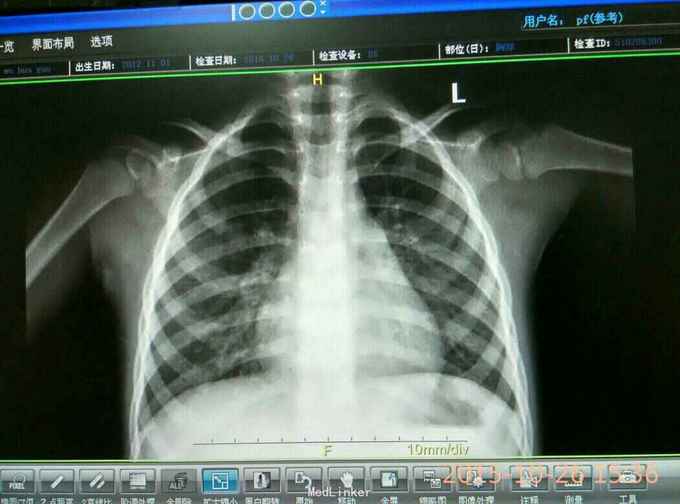

患儿,女,3岁 主诉:咳嗽5天,喘息2天 病史:患儿于5天前因受凉出现咳嗽,阵发性,有疾不易咳出,偶尔咳出黄痰。在外院检查:肺炎支原体阳性,CRP、均正常。静点阿奇霉素针3天,症状无减轻,并出现发热,咳嗽伴喘息。门診拍胸片以"肺炎"收住院。

体格检查:T,37.7℃,p:142次/分,R:25次/分,Bp:86/56mnHg,神志清,精神可,咽腔稍充血,双侧扁桃体无肿大,颈软,胸廓对称,无畸形,双肺呼吸音粗糙,可闻及痰鸣音,.心前区无异常隆起及凹陷,心尖搏动无弥散,听诊:心率:142次/分,各瓣膜无病理性杂音,神经系统未引出病理反射。化验:痰培养(-),MP-Ab(-),结明三项(-),ALP增高。CRP(-)血常规,胸片见图。

大叶性肺炎 治疗:抗感染::哌拉西林他唑巴坦加痰热清静脉点滴,止咳平喘对症处理活疗7天症状无改善且加重,调整为舒普森加阿奇霉素联合,佐以止咳平喘,匹多莫德,维生素AD等支持疗法,又治疗7天,症状体征消失痊愈出院。

该病人由于症状不典型,比如: 精神好,无明显发热,肺部听诊无啰音,血常规始终正常,CRP正常,MP-Ab(-),虽然胸片明显,因此仍按普通肺炎治疗,但无好转且加重。之后改用双联抗生素后症状迅速好转,二周痊愈。提示胸片检查的重要性,同时对大叶性肺炎双联抗感染的必要性,因为一些病原学检查会受外界因素影响而出现假阴性,如果只依赖化验检查而忽视临床表现则会而延误诊治。